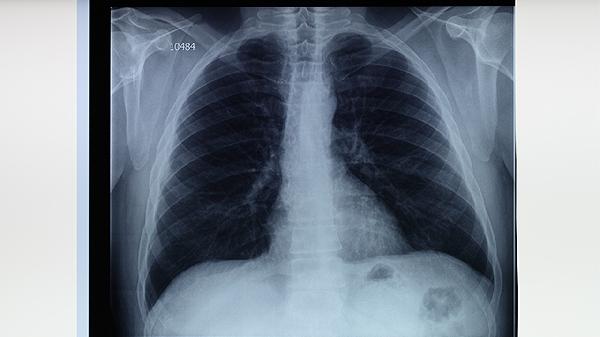

肺结核患者除规范用药外,需保证充足营养摄入,每日蛋白质应达到每公斤体重1.2-1.5克,优先选择鸡蛋、鱼肉等优质蛋白。适当进行有氧运动如散步可改善肺功能,但需避免剧烈活动。居住环境要保持通风,佩戴口罩减少传播风险。治疗期间严格戒烟戒酒,定期复查胸部影像学和痰菌检查,全程治疗通常需要6-9个月,擅自停药可能导致治疗失败或复发。